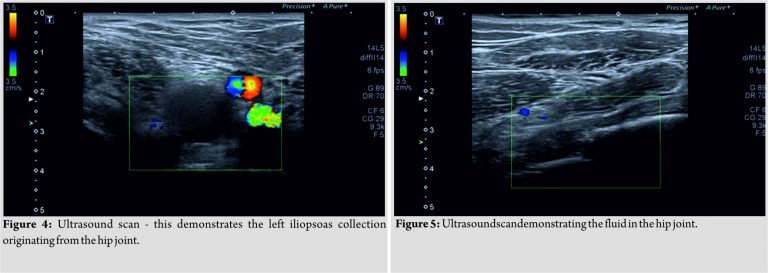

On examination, there was marked left hip tenderness with pain on hip flexion and rotation, as well as an antalgic gait. The left knee was not hot, swollen or tender and did have a full, normal range of movement. Similarly, examination of the lumbarsacral spine did not reveal any abnormality. Surrounding the left hip, there was no swelling, erythema, and no local signs of injury or infection. The patient’s physiological parameters (temperature, blood pressure, heart rate, respiratory rate, and oxygen saturations) were all within normal ranges. Laboratory investigations demonstrated a normal white cell count (WCC) (6.74 × 109/l) and a C-reactive protein (CRP) of13 mg/l. The CRP level was slightly elevated, and given the history of long-termimmunosuppression (due to the HIES) this had to be and was not taken lightly. As mentioned previously, WJ was admitted to the ward with a report of the private pelvis MRI scan that had been performed. Despite this, a plain radiograph of the pelvis was still obtained (Fig. 3), and this showed multiple sites of calcified apophyses, with an aspherical femoral head and dysplastic acetabulum. Abscess formation, including cold abscesses, can be quite common within HIES patients [5]. For this reason, the patient underwent an ultrasound (US) guided aspiration of the left hip (Fig. 4 and 5). This procedure was carried out by a consultant radiologist, with a specialinterest in musculoskeletal imaging. During the procedure, only a small amount of fluid was found to be in the left hip joint. However, interestingly, in addition to the left hip, a fluid collection was also seen within the left iliopsoas. From both sites, 20ml of blood-stained fluid was aspirated. No pus was seen. The fluid sample was sent to the laboratory for microscopy, culture,and sensitivity and after prolonged incubation, no organisms were grown. Over the course of the ensuing 3days, serial blood tests demonstrated a fall in the CRP to within normal range, with no increase in the WCC. Following the US-guided procedure, WJ noticed a significant improvement in his left hip. Mobilizing was a lot more comfortable, and again no abnormality in the physiological parameters was recorded. WJ was discharged home, having not required any antibiotics. Follow-up from the orthopaedic and the immunology teams had been put in place before discharge.